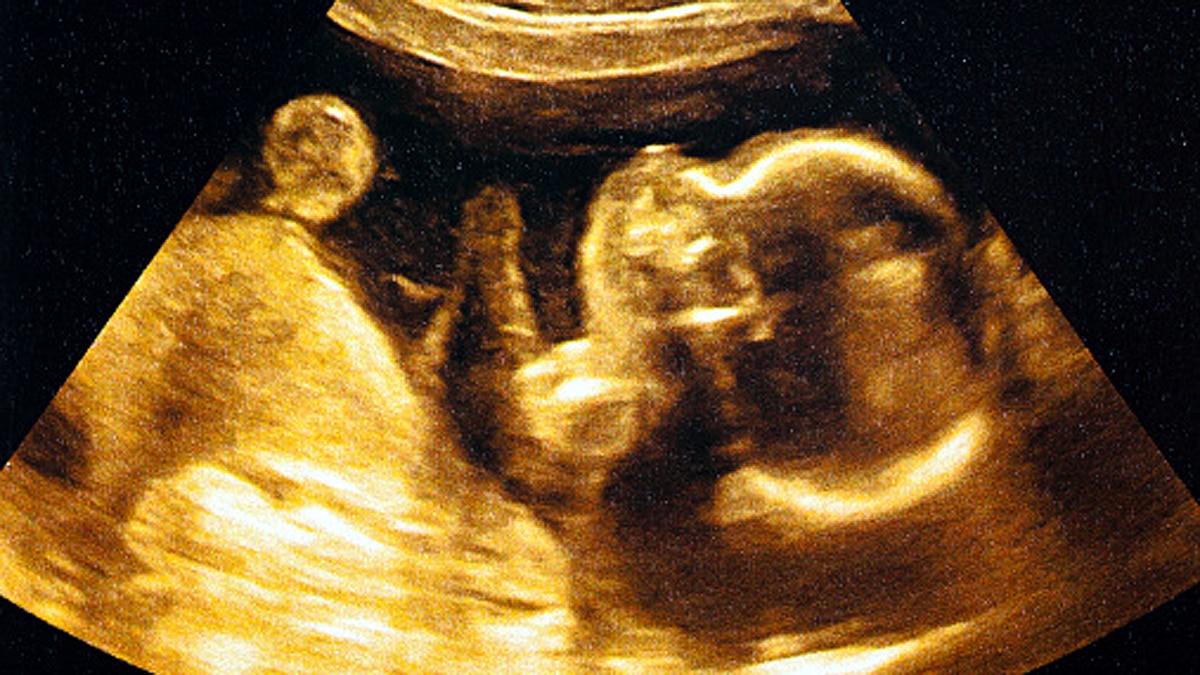

गर्भवती महिलाओं के लिए वैज्ञानिकों ने एक ऐसा ब्लड टेस्ट खोजा है, जिससे गर्भवती महिला और उसके पेट में पल रहे बच्चे से संबंधित दिक्कतों और बीमारियों के बारे में पता चल जाएगा. हालांकि, इंसान के गर्भधारण की प्रक्रिया को समझना आज भी वैज्ञानिकों के लिए एक चुनौती है. अब तक बीमारियों और दिक्कतों का पता करने के लिए वैज्ञानिक भ्रूण से डीएनए लेते थे. या फिर आरएनए का सैंपल लेकर जांच करते थे. पर एक ब्लड टेस्ट से गर्भधारण के समय होने वाली प्री-एक्लैम्पसिया (Pre-Eclampsia) नामक दिक्कत का पता चल जाएगा.  (फोटोः गेटी)

यह स्टडी हाल ही में Nature जर्नल में प्रकाशित हुई है. असल में गर्भावस्था के दौरान मां और उसके बच्चे का स्वस्थ रहना बेहद जरूरी है. गर्भावस्था यानी प्रेगनेंसी के दौरान महिलाओं को प्री-एक्लैम्पसिया (Pre-Eclampsia) नामक दिक्कत का सामना करना पड़ता है. यह दिक्कत आमतौर पर दूसरी बार गर्भधारण करने पर आता है. इसका असर बच्चे की सेहत पर पड़ता है.  (फोटोः गेटी)

दुनिया में करीब 15 प्रतिशत गर्भवती महिलाओं को यह बीमारी होती है. इसका पता करने के लिए वैज्ञानिकों ने एक ब्लड टेस्ट खोजा है. जिससे प्री-एक्लैम्पसिया समेत कई बीमारियों का पता चल जाएगा. इस बीमारी की वजह से पूरी दुनिया में मां और बच्चे की मौत भी हो जाती है. कोविड काल में तो यह खतरा और भी ज्यादा बढ़ जाता है. जिससे मां और बच्चे दोनों को नुकसान हो सकता है.  (फोटोः गेटी)

प्री-एक्लैम्पसिया (Pre-Eclampsia) एक ऐसी बीमारी है, जो गर्भवस्था के दौरान होती है. इसमें महिलाओं के ब्लड प्रेशर बढ़ जाता है. पेशाब में प्रोटीन आने लगता है. पैरों और बांहों में सूजन आ जाती है. इसे प्री-एक्लैम्पसिया कहते हैं. स्थिति गंभीर होने पर एक्लैम्पसिया कहा जाता है. यानी सही समय पर इसका इलाज न हो तो मां और बच्चे की जान को खतरा बना रहता है.  (फोटोः गेटी)

प्री-एक्लैम्पसिया (Pre-Eclampsia) के लक्षण आमतौर पर 20वें हफ्ते के आसपास दिखने लगते हैं. इसके लक्षणों में शामिल हैं- हाई ब्लड प्रेशर, धुंधला दिखना, सीने में जकड़न और दर्द, सांस लेने में दिक्कत, सिर दर्द, चेहरे, हाथ और पैर में सूजन. इसलिए जब भी महिलाओं को यह दिक्कत दिखाई दे या ऐसे लक्षण महसूस हो तो सबसे पहले किसी बेहतरीन डॉक्टर को दिखाएं. ताकि समय रहते इसका इलाज किया जा सके.  (फोटोः गेटी)

कोरोना काल में अगर कोई महिला गर्भवती है तो उसे प्री-एक्लैम्पसिया (Pre-Eclampsia) जैसी दिक्कतों का खास ख्याल रखना होगा. क्योंकि कोविड संक्रमण होने पर सीने में सबसे ज्यादा असर होता है. गर्भावस्था के दौरान प्री-एक्लैम्पसिया विकसित होने की आशंका 60 फीसदी से ज्यादा होती है. इसके अलावा एचईएलएलपी सिंड्रोम, हीमोलिसिस यानी रेड ब्लड सेल्स का टूटना, लिवर एंजाइम का बढ़ना और प्लेटलेट्स का कम होना शामिल है.  (फोटोः गेटी)

प्री-एक्लैम्पसिया (Pre-Eclampsia) से पीड़ित गर्भवती महिला का खास ख्याल रखा जाना चाहिए. उसे सही समय पर डॉक्टर से दिखाना चाहिए. सही दवाएं और खानपान होना चाहिए ताकि उसके शरीर में उच्च स्तर की एंटीबॉडी का निर्माण हो सके. (फोटोः गेटी)